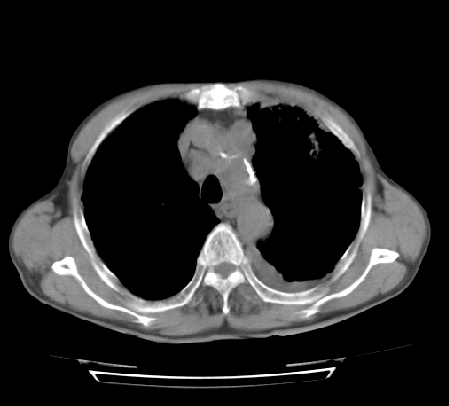

以下是引用hhcckk在2009-5-29 14:58:00的发言:[br]左上周围型肺癌,左肺门、纵隔淋巴结转移,左侧胸腔积液,左侧肋骨转移[br]

以下是引用ct诊断高手在2009-5-29 13:50:00的发言:[br]考虑左侧中央型肺癌,阻塞性肺炎伴肺不张。纵隔淋巴结转移。慢支 肺间质纤维化肺气肿。左侧胸腔积液。左侧肋骨转移?